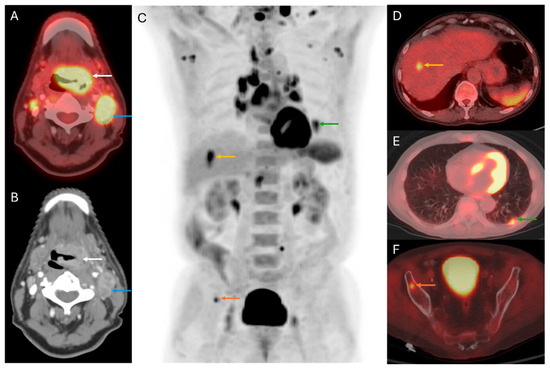

3. Primary Tumor Staging

5. Distant Disease Detection